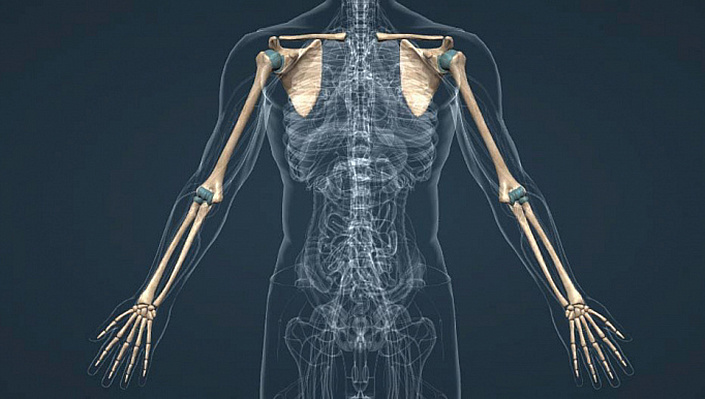

Сколько же костей содержит рука? Человеческая рука в общей сложности вобрала в свою структуру 32 кости. При этом по силе руки уступают ногам, но первые компенсируют это большей подвижностью и способностью совершать множественные движения.

Анатомические отделы руки

Вся рука в целом включают в себя следующие отделы.

Плечевой пояс, состоящий из частей:

Предплечье, включающее кости:

Кисть имеет в себе кости:

Как устроены кости плечевого пояса?

Строение и функции плечевого пояса

Плечевой пояс является местом перехода туловища к верхним конечностям. Он состоит из двух лопаток — правой и левой — и такого же количества ключиц. Благодаря им обеспечивается поддержка позиции рук относительно туловища, а также их движение по трём различным осям.

Ещё одна косточка плечевого пояса — ключица — относится к трубчатым и имеет слегка изогнутую S-образную форму. Она располагается горизонтально и слегка наклонена вниз в области шеи. Ключицы служат связующим звеном между грудиной и лопатками, а также поддерживают мышечный каркас плечевого пояса.

Анатомия костей и мышц руки в области плеча

Плечо — верхняя часть руки, соединённая непосредственно с туловищем. В локтевом суставе она переходит в другую область — предплечье. Плечо состоит из крупной трубчатой кости, форма которой меняется в зависимости от зоны: если ближе к лопатке срез плечевой кости имеет практически идеально округлую форму, то ближе к предплечью она напоминает скорее треугольник со скруглёнными углами.

Анатомия предплечья

Область верхней конечности, начинающаяся у локтевого сустава и заканчивающаяся запястьем, называют предплечьем. Её образуют две косточки различного диаметра — лучевая и локтевая. Срез локтевой кости имеет трёхгранную форму с утолщением в верхнем конце, в месте сочленения с плечевой костью. Спереди локтевого сустава есть небольшая блоковидная вырезка, которая ограничивает разгибание локтя, препятствуя нефизиологичному перерастяжению мышц предплечья и плеча.

Лучевая кость, напротив, утолщается книзу, в запястном суставе. Они соединены с локтевой косточкой подвижно, благодаря чему кисть может вращаться до 180 градусов.

Кости руки человека: анатомия кисти

Кисть — одна из самых анатомически сложных областей руки. Условно её можно разделить на 3 функциональные зоны: